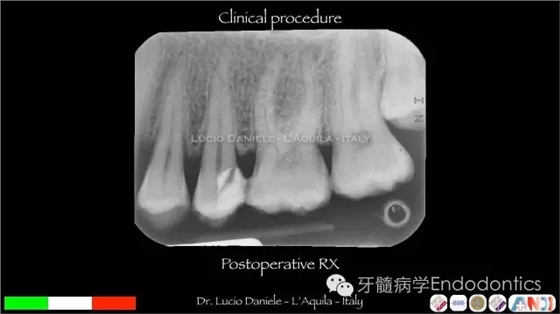

圖24.術后X線片